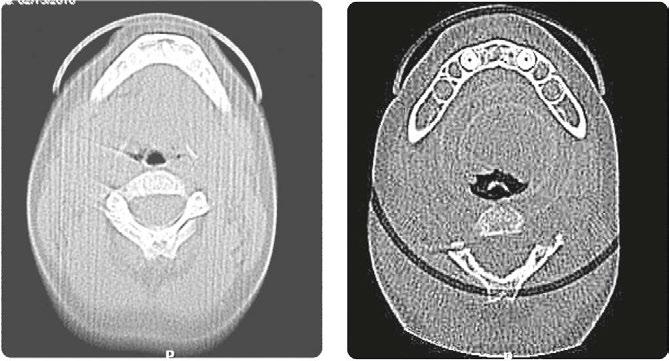

Over 10 years ago, we began Orthotropic® treatment for a 5 year, 3-month-old boy with a diagnosis of Pierre-Robin Sequence, Obstructive Sleep Apnea (OSA), and Failure to Thrive (Figure 1). With lack of forward development of the face com-

monly seen in Pierre-Robin patients, his airway was compromised, resulting in OSA. The Failure to Thrive diagnosis likely resulted from insufficient growth hormone being released during the deeper stages of sleep. This treatment began before any permanent teeth erupted. Our goal was to eliminate OSA.

Orthotropics® uses removable appliances to laterally expand the upper arch while simultaneously advancing the upper anterior teeth to their proper place in the face. Then the mandible is developed forward. Orthotropics® is my preferred treatment in cases like this because it negates the head gear-effect producing better facial balance5 and also can result in substantial airway improvements (Figure 2).6

Figure 1: Pretreatment gallery Figure 3: Today, he’s a tennis player Figure 2: Pre- and posttreatment airways